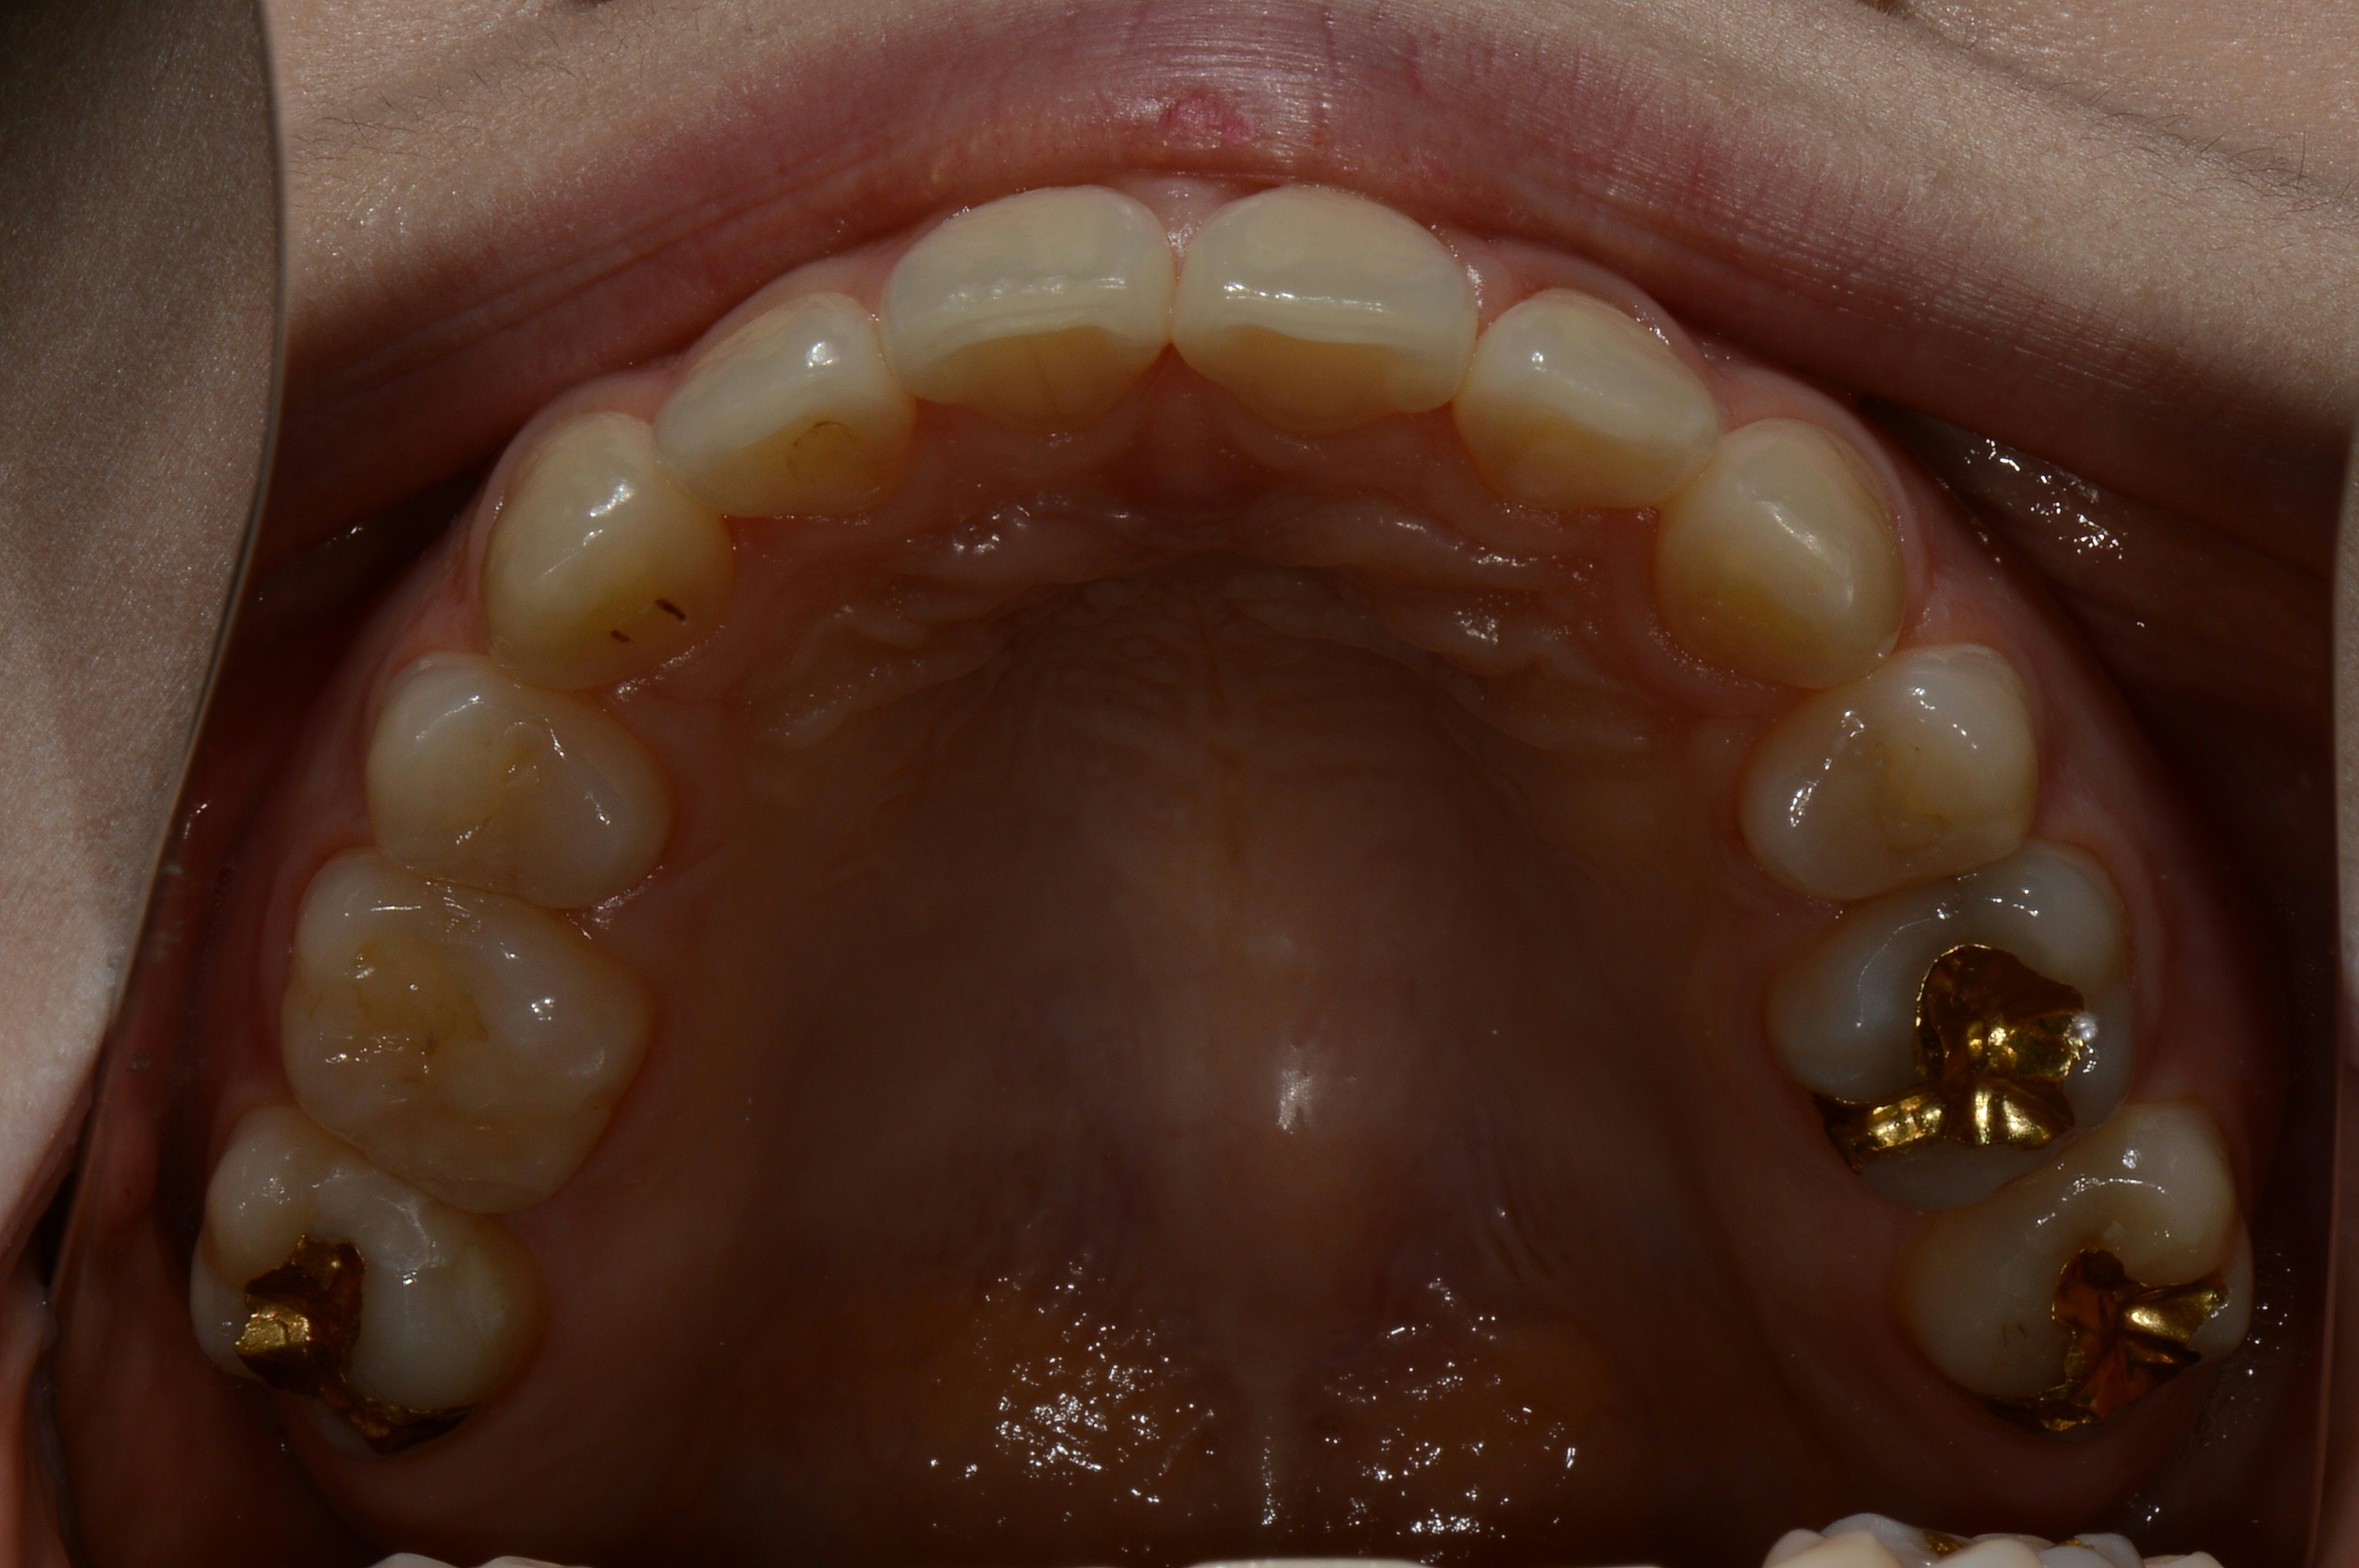

치료 전 사진입니다.